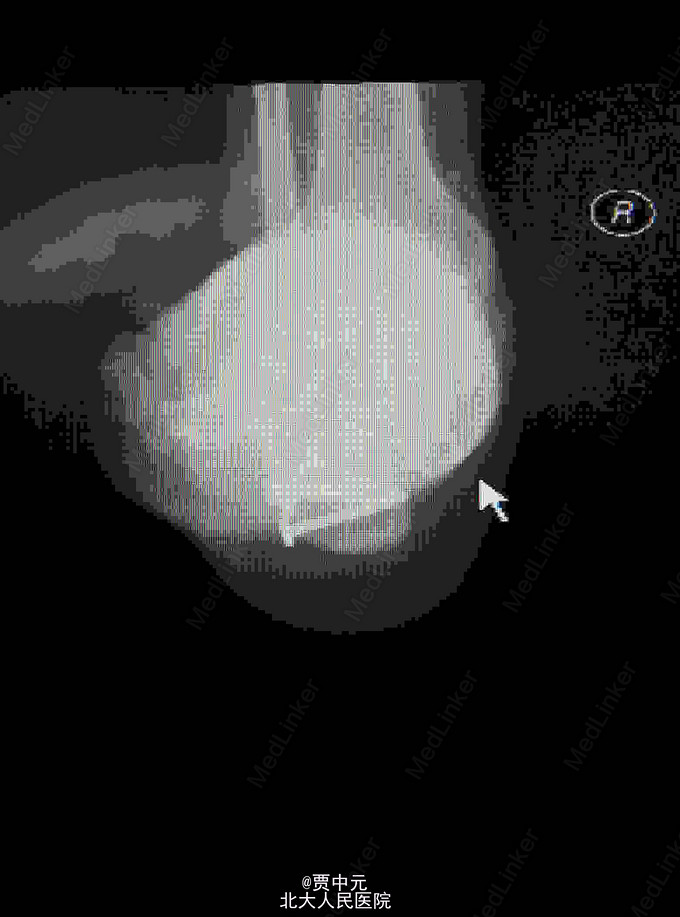

男性,31岁,主因“高处坠落伤致右足跟部疼痛,活动受限1天”于急诊以“右侧跟骨骨折”收入院。 一.病例特点 1.青年男性,高处坠落史。 2.患者约1天前自高处坠落右足着地,当时未昏迷,自觉右足肿痛,不敢活动,在当地医院拍片示:右侧跟骨骨折,为进一步手术治疗收住院。自入院来,患者无发热及胸闷憋气及腹痛症状

入院查体:右足跟部肿胀,局部皮下淤血,压痛,叩击痛,趾端血运可,足趾感觉及活动可,余肢体未见明显异常。 X线:右侧跟骨骨折(外院)

右侧跟骨骨折:高处坠落伤1天,查体:右足跟部肿胀,局部皮下淤血,压痛,叩击痛,趾端血运可,余肢体未见明显异常。 X线:右侧跟骨骨折(外院),根据外伤史,查体及X线检查,故此诊断明确